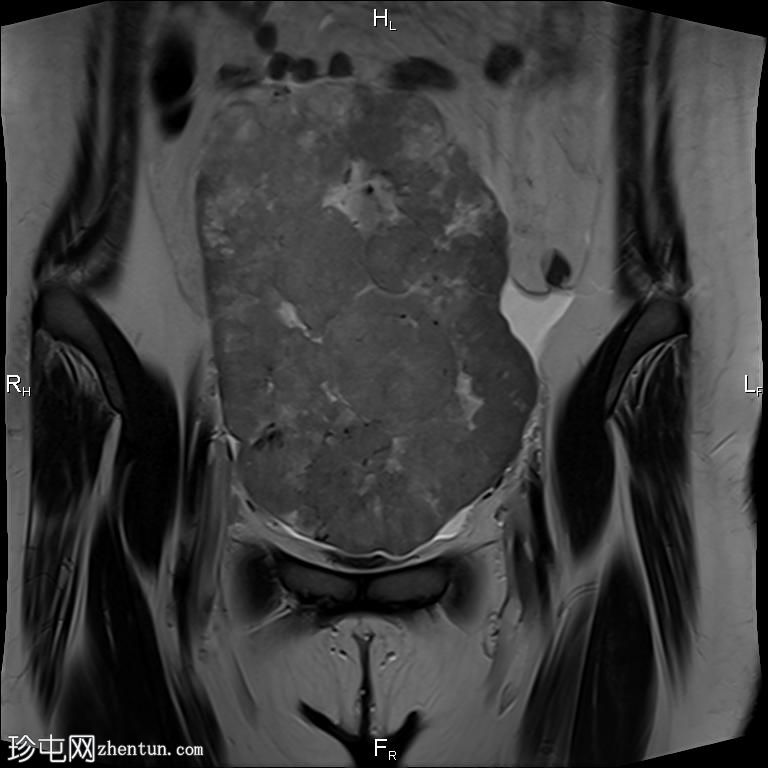

冠状位

T2

盆腔内可见一巨大多分叶实性肿块,内部有隔膜,T2WI信号不均匀,T1WI信号不均匀,呈低信号。肿块内散在分布囊性/坏死性病变。

肿块外可见子宫和右侧卵巢,肿块似源自左侧卵巢。该肿块压迫膀胱和两侧远端输尿管,并导致肠管和血管结构移位,但无侵袭或包裹征象。

造影后,肿块呈不均匀强化,隔膜强化。

远端髂腹旁和两侧髂骨旁区域可见少量肿大淋巴结。